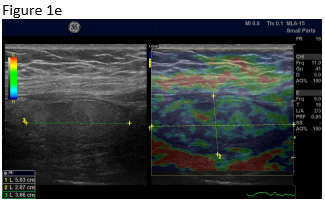

Figure 1: B-mode ultrasound using low frequency (a) and high frequency (b) revealed an isoechoic mass with a hypoechoic circumference. The mass was not adher-ent to the colon. Contrast enhanced ultrasound using low frequency (c) and high frequency (d) revealed that it was a non-enhancing segment of the omentum. Strain elastography showed that the lesion was stiffer than its sur-rounding tissue.

Transabdominal ultrasound typically shows a focal solid and non-compressible, solid, hy-perechoic ovoid lesion sometimes with a peripherally located hypoechoic (inflammatory) rim [(1-3, 9)]. A typical ultrasound image of omental infarction is characterized by: a slightly or moderately hyperechoic plaque-like mass greater than 35 - 50 mm located under the ab-dominal integuments to the right of the navel. Appendagitis tends to be smaller. The mass is sensitive to compression but with no visible compressibility [(10)]. Sometimes, the lesion is surrounded with a hypoechoic rim, or slight amounts of fluid are found in the vicinity. Colour Doppler Imaging (CDI) typically reveals absence of blood flow in the mass lesion similar to appendagitis and other ischemic diseases [(15, 27-30)] but contrast enhanced ultrasound is much more sensitive [(26, 31-39)]. However, vessels on the periphery of a central hypoechoic necrotic area have been observed in children with this pathology [(10)]. The pathological mass gives a similar US image to that of necrotic fat tissue at other abdominal sites. Most often isoechoic to the surrounding tissue the appearance varies from slightly hyperechoic to more often centrally located hypoechogenicity [(15, 40, 41)]. The echogenicity depends on the in-flammatory process and inflammatory vessels or infarct. It is typically iso- or hyperechoic, non-vascularized, sensitive and shows no compressibility [(11)]. Strain elastography and shear wave elastography [(42-51)] may reveal stiffer tissue than the surrounding. Ultrasound typi-cally shows an oval shaped and non-compressible painful mass directly under the abdominal wall.